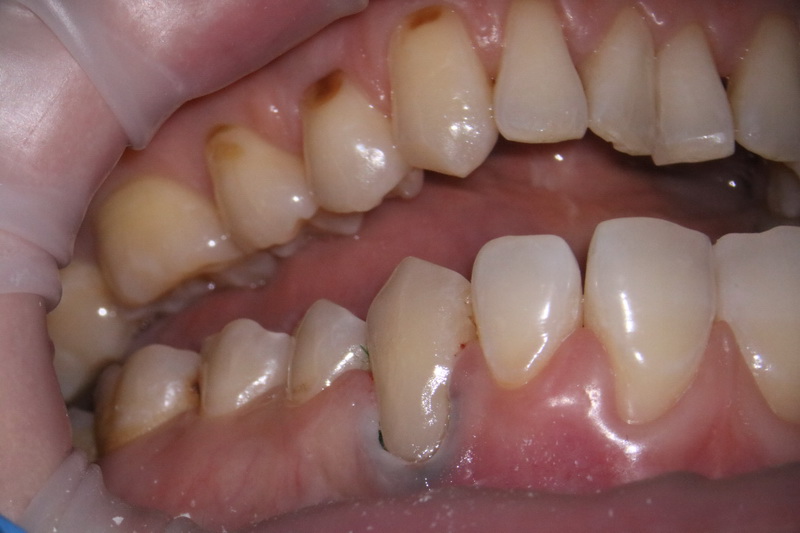

Клиноподібний дефект – це некаріозний дефект емалі, що розташовується на вестибулярній поверхні зуба в пришийковій зоні, тобто зі сторони губ та щік біля ясен.

Травмування може бути як механічне, так і внаслідок порушень роботи органів ШКТ через які відбувається заброс шлункового соку в порожнину рота. Також емаль може руйнуватися під час чищення – це результат неправильних рухів зубною щіткою по емалі, яка внаслідок цього стирається. А зворотній заброс шлункового соку призводить до демінералізації емалі всіх зубів і як наслідок утворення клиноподібних дефектів.

Клиноподібний дефект сам по собі зникнути не може і з часом це призводить до повного стирання твердих тканин в пришийковій ділянці і як наслідок виникають переломи або сколи зубів.

Симптоматично можна зняти гіперчутливість цих зубів, відреставрувати ці дефекти за допомогою композитної чи керамічної реставрації. А щоб подіяти на причину ми маємо виправити вади прикусу, що призводять до перевантаження зубів або навчити пацієнта правильним навичкам гігієни.